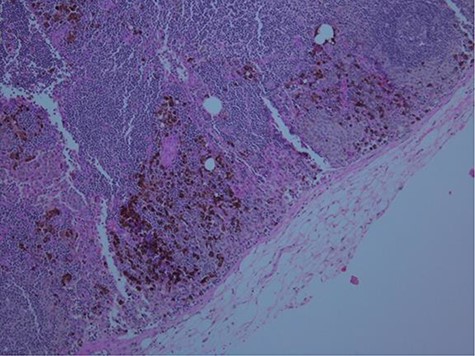

Following the results of the biopsy, the patient was referred to the oncology service where the diagnosis of splenic lymphoma was proposed, and the patient was referred to us for splenectomy. He subsequently underwent an uncomplicated hand-assisted laparoscopic splenectomy. Gross pathological examination demonstrated a deeply pigmented spleen (Fig. 2), and histopathologic examination of the spleen revealed positive staining for HMB-45 (Fig. 3), S-100 and Ki-67 suggestive of metastatic melanoma. This diagnosis was confirmed by a quaternary medical center that also examined the specimen.

Gross formalin-fixed pathological specimen fragment with deeply pigmented melanocytes.